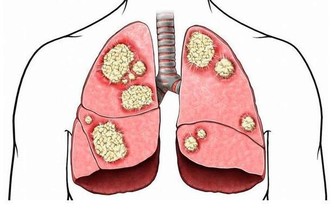

在放屁時不應出現不適感,氣味雖然難聞但不會極端惡臭。如果發現自己在排氣時,明顯感到腹痛,或是氣味比較異常,那麼應當立即去醫院進行相應檢查,食物不耐受和結腸癌等疾病都會引起這類病症。